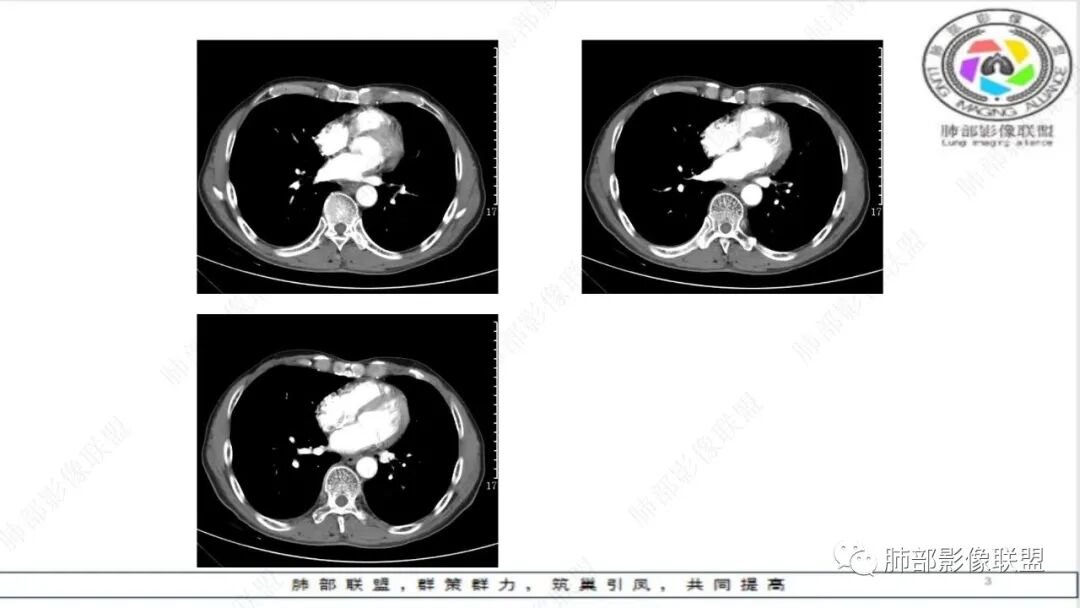

老年男性,肺气肿,左肺门及纵膈多发肿大淋巴结融合,包埋血管,冰冻,左肺上叶支气管受压变窄,左肺上叶胸膜下楔形实变,梗死灶?考虑小细胞癌,鉴别腺癌

晨读:老年男性,肺气肿背景,冰冻,血管挤压,恶,小,左肺胸膜下原发?肺栓塞?

冰冻纵隔,冰冻肺门,血管变细、变直,未见明显阻塞性肺炎,结合老年男性,考虑小细胞肺癌。

纵隔内及左肺门淋巴结肿大,冰冻纵膈,肺动脉包绕受压,支气管受压变窄,呈针孔样。双肺上叶结节及条索考虑陈旧结核。老年男性,慢支肺气肿背景,考虑小细胞肺癌。左肺上叶后段大片实变,不符合小细胞肺癌原发灶,二元论感染灶?肺栓塞?

晨读:男,65,咳喘1月余,加重3天。胸部CT:纵隔、肺门多发淋巴结肿大融合,冰冻纵隔,冰冻肺门,大血管包埋挤压,左肺A主干变窄。平扫密度较均匀,不均匀强化,灶性低密度。右上肺多发实性结节,中轴间质分布;左上叶针孔状支气管,后段胸膜下近楔形斑片影,融冰?考虑Ca,SCLC,并左上叶PTE?鉴别淋巴瘤。

纵隔及左肺门肿大、融合淋巴结,轻度不均匀强化,肺动脉、支气管包绕受压,左肺上叶叶间胸膜下条状实变,边界清,考虑小细胞肺癌

老年男性,肺气肿。影像:冰冻纵膈及肺门,大病灶内小灶状坏死,少部分病灶明显坏死,肺动脉包绕受压,支气管受压变窄,呈针孔样改变。考虑小细胞肺癌,鉴别淋巴瘤,转移瘤。

晨读,老年男性,肺气肿背景,左肺门及纵隔内多发肿大淋巴结,部分融合、包埋血管,冰冻状,左肺上叶支气管受压变窄。双肺散在小结节,左肺上叶胸膜下楔形实变。考虑恶性病变,小细胞肺癌,鉴别淋巴瘤、转移瘤

老年慢性,肺气肿背景,纵隔左肺门明显多发肿大淋巴结且融合,密度相对均匀,增强后轻中度强化,偏纵隔右侧淋巴结坏死明显,左肺支气管可见受压变窄,呈针孔样改变。左肺上叶叶间裂上方山丘状混合磨玻璃病灶,内密度不均可见空泡。考虑小细胞肺癌(娘小崽大)。

老年男性,肺气肿背景,左肺上叶后段斑块病灶,边缘清膨隆感,有强化,蜂窝状破坏,胸膜下载赃,纵隔及左肺门多发淋巴结肿大及强化,部分坏死,融合呈大团块,左主支气管外压变窄,并包埋左肺动脉受压,方向左肺上叶后段低分压腺ca并左肺门及纵隔淋巴结转移肿大,右肺上叶转移结节,建议超声支气管镜,左肺门淋巴结活检。

老年男性,娘小崽大,冰冻纵膈,小山丘征,支持恶性肿瘤中小细胞肺癌。

冰冻肺门,冰冻纵隔,肺A包绕受压,针孔样支气管,典型小细胞癌

联盟晨读病例:左肺门软组织肿块,纵隔淋巴结肿大相互融合,左肺上叶支气管狭窄,血管受压,左肺上叶阻塞性肺炎,考虑左肺上叶中心型肺癌伴纵隔淋巴结肿大,左肺上叶阻塞性肺炎。小细胞癌。